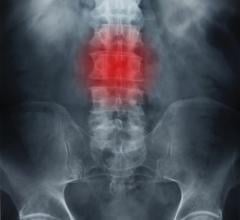

September 18, 2023 — According to an accepted manuscript published in the American Journal of Roentgenology (AJR), an ...